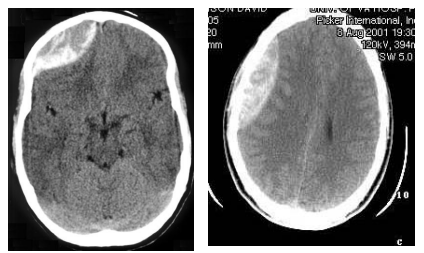

・慢性硬膜外血腫:硬膜と頭蓋骨の間に血腫形成。凸レンズ型の血腫。

慢性硬膜外血腫のCThttps://www.uic.edu/com/ferne/pdf/acep_2005_peds/perron_ich_acep_2005_peds_course.pdf

・慢性硬膜下血腫:軽微な外傷から1ー2ヶ月経ってから発症することも少なくない。三日月型の血腫。

慢性硬膜下血腫のCThttps://www.uic.edu/com/ferne/pdf/acep_2005_peds/perron_ich_acep_2005_peds_course.pdf